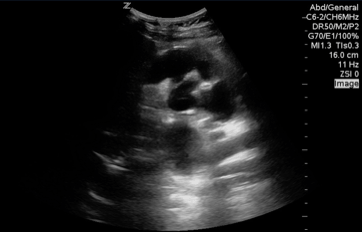

QA of the Day: interpreted as probable SBO. Severe hydronephrosis. #pocus #foamus